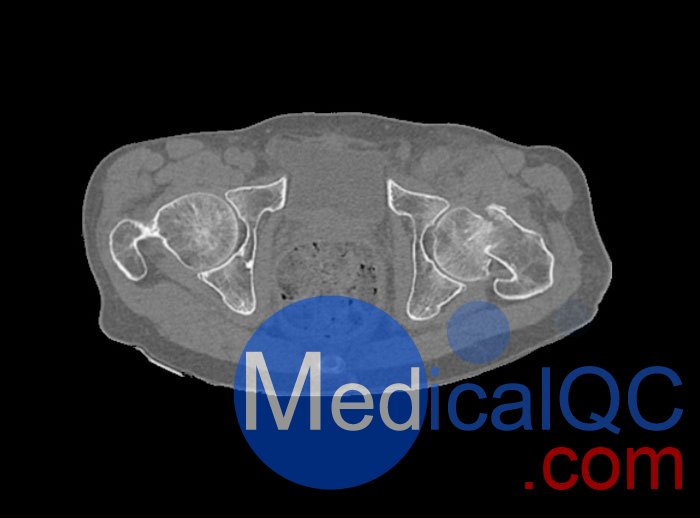

WEK54-01股骨頸骨折骨盆模型,WEK54-01骨盆模體模擬沒有靜脈造影劑的骨盆(天然)。它覆蓋了整個骨盆,直到第五腰椎。

WEK54-01股骨頸骨折骨盆模型,WEK54-01骨盆模體提供了對軟組織和骨組織的詳細(xì)而逼真的模擬??障吨刑畛渲s-160HU的纖維素-聚合物復(fù)合材料。

骨骼和軟組織的逼真模擬。